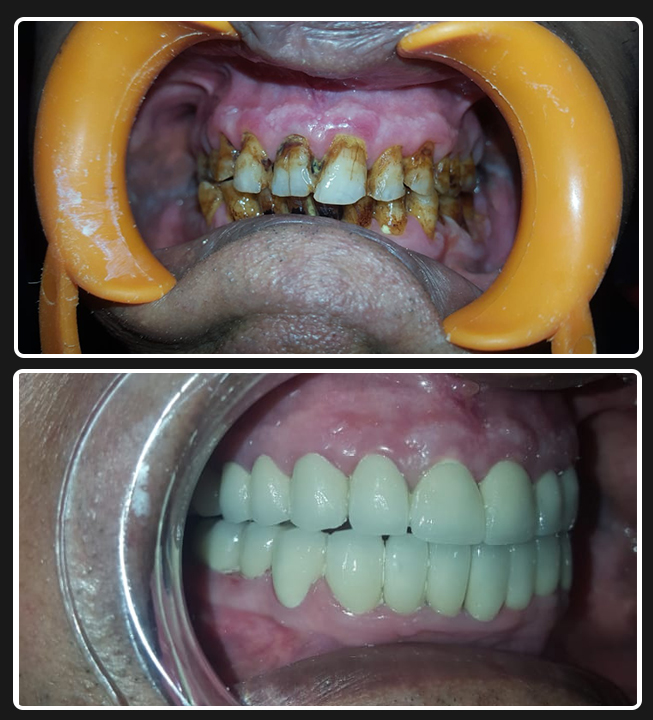

Full Mouth Zirconia (All-Ceramics)

Case 1